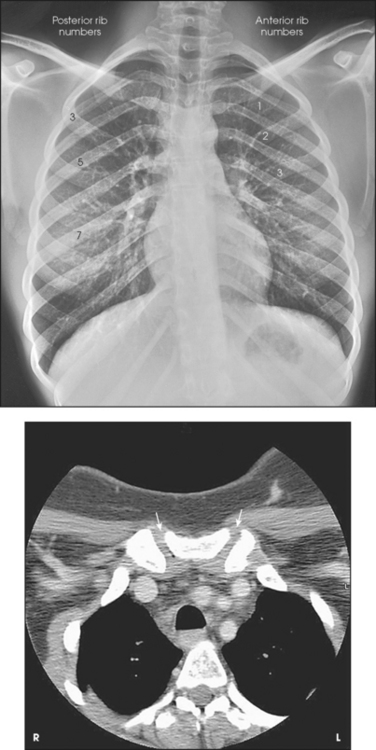

The 12 pairs of ribs are numbered consecutively from superiorly to inferiorly (Fig. 9-4; see Figs. 9-1 and 9-2). The rib number corresponds to the thoracic vertebra to which it attaches. Each rib is a long, narrow, curved bone with an anteriorly attached piece of hyaline cartilage, the costal cartilage. The costal cartilages of the first through seventh ribs attach directly to the sternum. The costal cartilages of the 8th through 10th ribs attach to the costal cartilage of the 7th rib. The ribs are situated in an oblique plane slanting anteriorly and inferiorly so that their anterior ends lie 3 to 5 inches (7.6 to 12.5 cm) below the level of their vertebral ends. The degree of obliquity gradually increases from the 1st to the 9th rib and then decreases to the 12th rib. The first seven ribs are called true ribs because they attach directly to the sternum. Ribs 8 to 12 are called false ribs because they do not attach directly to the sternum. The last two ribs (11th and 12th ribs) are often called floating ribs because they are attached only to the vertebrae. The spaces between the ribs are referred to as the intercostal spaces.

The position of the diaphragm varies with body habitus: It is at a higher level in hypersthenic patients and at a lower level in asthenic patients (Fig. 9-9). In sthenic patients of average size and shape, the right side of the diaphragm arches posteriorly from the level of about the 6th or 7th costal cartilage to the level of the 9th or 10th thoracic vertebra when the body is in the upright position. The left side of the diaphragm lies at a slightly lower level. Because of the oblique location of the ribs and the diaphragm, several pairs of ribs appear on radiographs to lie partly above and partly below the diaphragm.